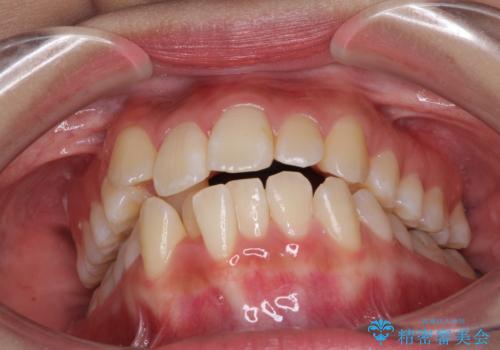

- 八重歯を気にして来院された患者様です。

上下ともに前突感と叢生が認められ、上顎の正中が著しく右側にずれていたため、上下左右第一小臼歯4本を抜歯し、ワイヤー矯正にて治療を行うこととしました。